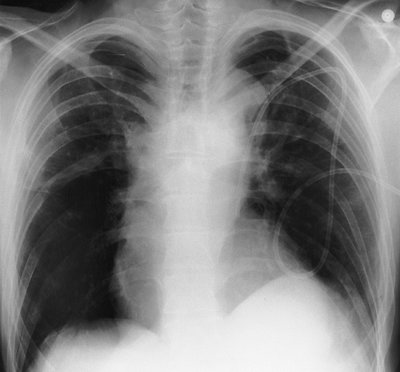

The preferred position of a CVP line tip is central to the venous valves, at the origin of the superior vena cava (SVC). The SVC is formed by the junction of the right and left BCVs. This junction lies to the right of midline at the level of the first intercostal space. The SVC is the preferred location for measuring CVP and avoiding catheter complications. The SVC is joined by the azygos vein posteriorly, just prior to entering the pericardium. Posterior orientation of the catheter tip suggests that it enters the azygos vein (Fig. 5-2).

A left-sided SVC, a normal anatomic variant, is found in 0.3% of normal individuals (Fig. 5-3). Eighty percent of such patients also have a right-sided SVC and 60% have a left BCV connecting the right and left SVCs (4). When a left SVC is present, both the right SVC and the left BCV are usually diminutive. The left SVC most commonly drains into the right atrium via a dilated coronary sinus.

FIGURE 5-1. Left subclavian vein, central venous catheter placement. A: Posteroanterior (PA) chest radiograph shows the catheter entering the left subclavian vein under the left clavicle, crossing the midline as it courses to the right and descending, with the tip positioned over the expected area of the superior vena cava (SVC) (arrow). B: Lateral chest radiograph shows the catheter curving anteriorly (arrow), where it crosses from the left brachiocephalic vein to join the right brachiocephalic vein. This anterior curve makes it possible to determine on a lateral radiograph that a catheter has been placed from the left side.

FIGURE 5-2. Azygos vein placement of central venous catheter. A: PA chest radiograph shows that the catheter tip is positioned over the expected area of the SVC. The tip is seen on end (arrow), however, which is a clue to azygos vein placement. The SVC is joined by the azygos vein posteriorly. B: Lateral chest radiograph shows the catheter coursing posteriorly, along the expected course of the azygos vein (arrows). Note how the more proximal portion of the catheter curves anteriorly (arrowhead), confirming placement from the left.

FIGURE 5-3. Left superior vena cava placement of central venous catheter. PA chest radiograph shows that, instead of crossing the midline to enter the SVC on the right, the catheter courses inferiorly to the left of the aortic arch, which is typical of placement within a persistent left SVC. This placement should be confirmed on a lateral chest radiograph to exclude aberrant positioning of the catheter within another venous or arterial structure.